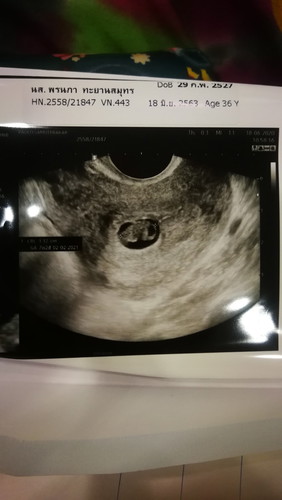

7week ตามหมอ 9 weekตาม แอฟ ไม่พบหัวใจเด็ก

อยากทราบว่าจะมีปาฏิหาริย์ไหม สัปดาห์หน้าหมอนัดเอาเด็กออก

13wค่ะก้อม่พบหัวใจเด็กค่ะ แต่หมอจะนัดอัตราซาว์อีกทีค่ะ ตอนนี้กังวลมากค่ะ

ทำใจไว้หน่อยนะคะ เคสน้องสาวแฟนหมอบอกหัวใจหยุดเต้นตอน 8w ก็ต้องเอาน้องออกค่ะ